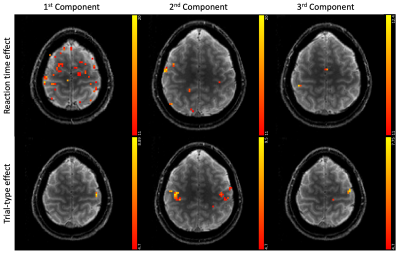

Figure 3 shows different slices covering the primary motor cortex overlayed by a statistical analysis of the component weights testing for significant effects (uncorr. p<0.001) of reaction time and trial-type in the component weights. Voxels with significant responses could be identified in all components.

F-score maps related to the component weights. All component weights were tested individually for a significant (uncorr. p<0.001) effect of reaction time and trial-type using a 2nd-level GLM. The color bars indicate the F-score.